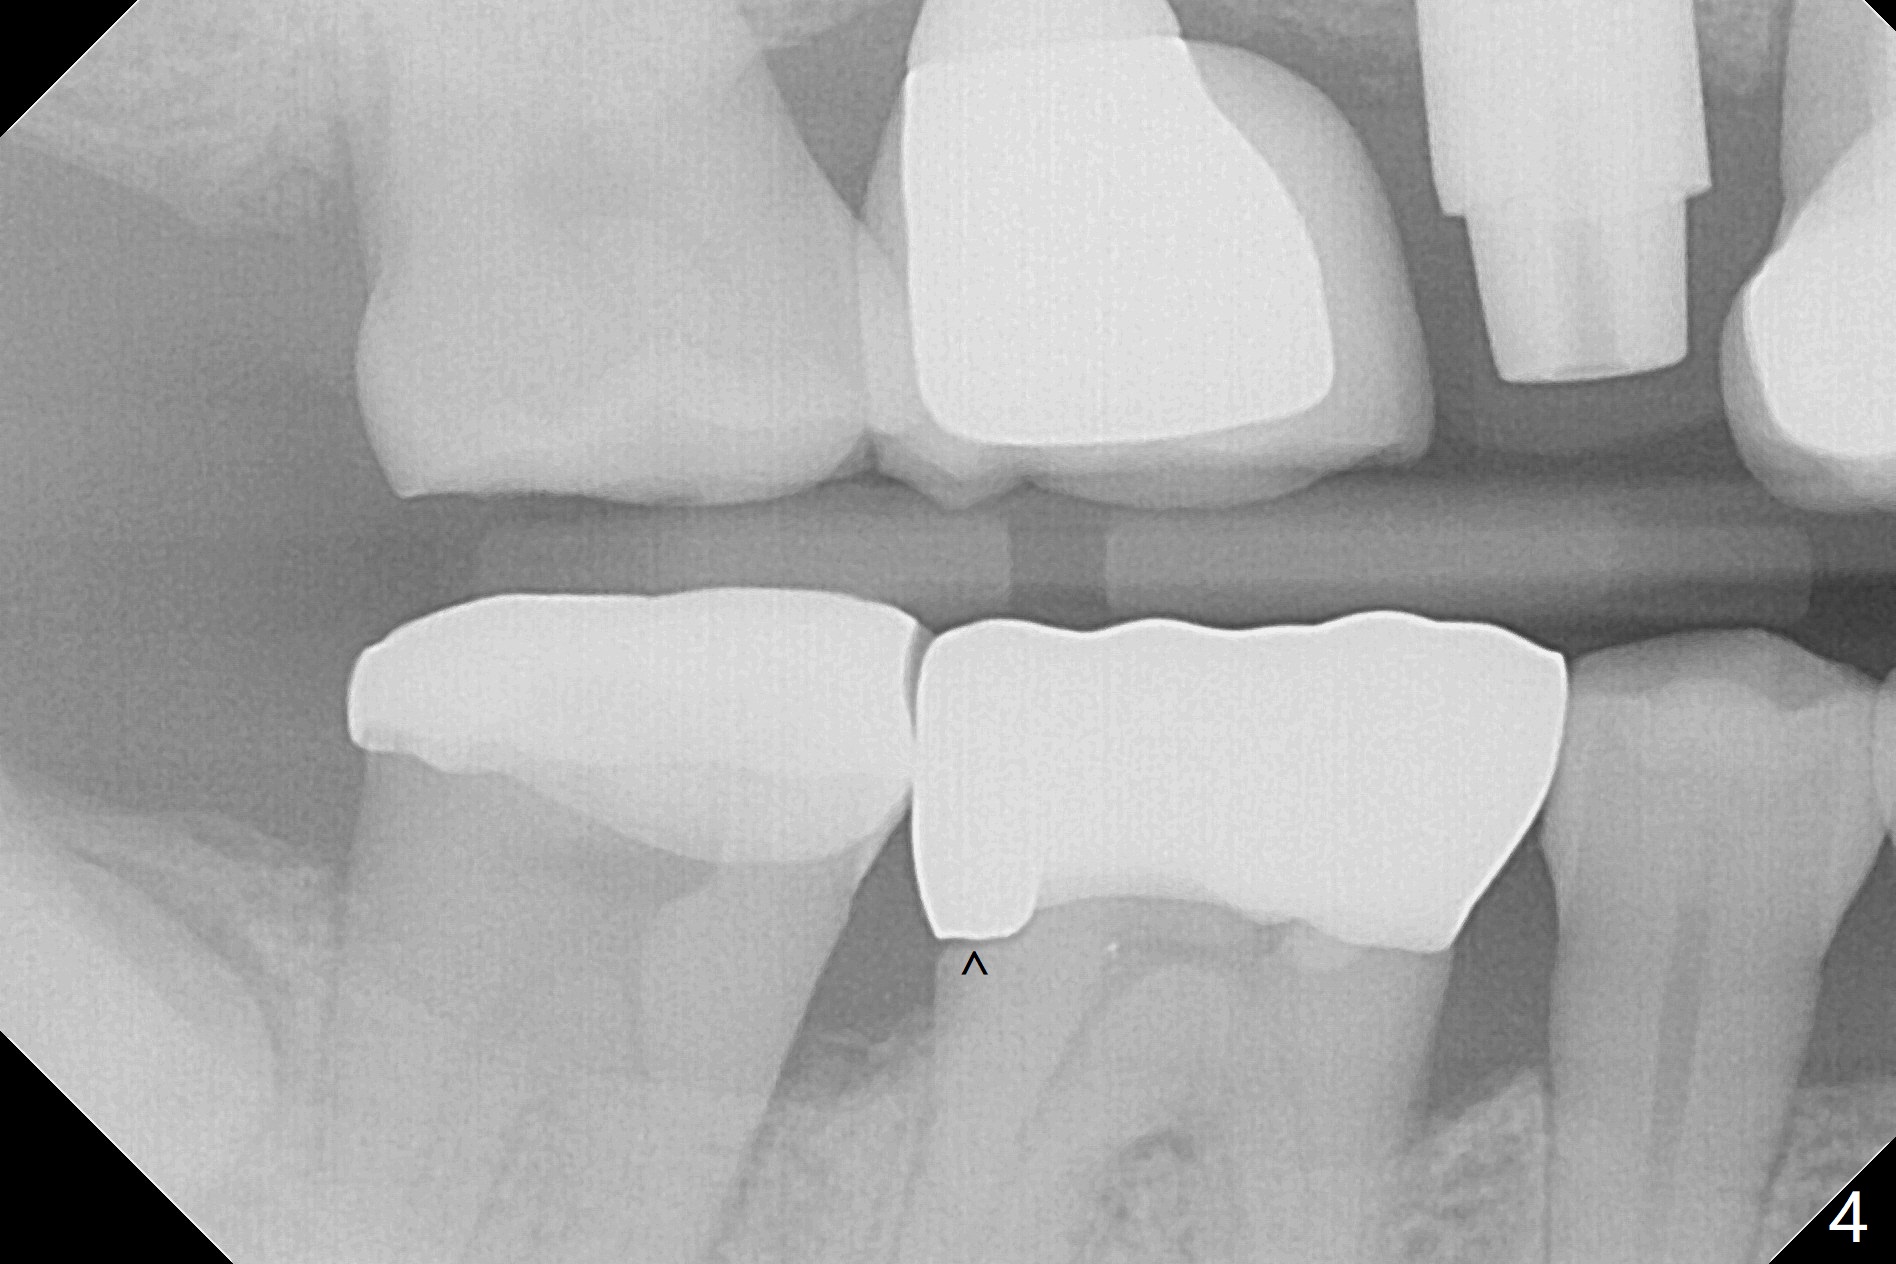

A 53-year-old man returns for #30 crown redo with distal open margin (Fig.1-3 arrowhead) after #4 implant. In addition to the distal margin caries, there is buccal one after removal of the existing crown. Composite build up is done for the buccal cavitation, whereas heavy chamfer margin is prepared distal. BW is taken immediately before cementation with open margin (Fig.4 ^). The latter disappears when the crown is cemented with pressure (Fig.5 arrow).